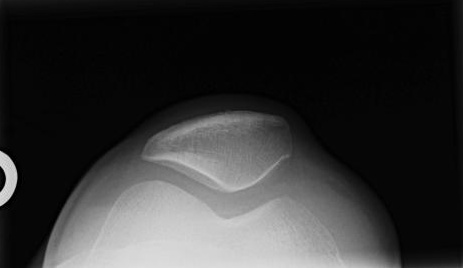

KNEE - SUNRISE RADIOGRAPH

When there is an intraarticular fracture of the tibial plateau or of one of the femoral condyles, bone marrow (mostly fat) migrates from the marrow space into the joint space. With fracture, blood also escapes, and a lipohemarthrosis is produced. Fat is less dense than blood, and it layers superior to it, producing the change in radiographic density referred to as a fat-blood interface (FBI sign).

CASE 1: These four radiographs are from a 50 year old male who fell 1 day prior to presentation. There is a tibial plateau fracture and a lipohemarthrosis. Click on each image for a larger view and notice the location of the fat-fluid level.

CLICK TO ENLARGE CLICK TO ENLARGE